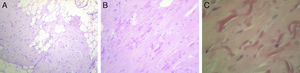

Case 4A 60-year-old with a history of osteoarthritis in the hands and thyroid nodules with hypothyroidism treated with levothyroxine consulted in January 2008 due to pain in the left subscapular region since one month earlier, which was increasing in size and spreading to the pectoral region, with limited movement of the left shoulder. Physical examination showed a painless mass of soft consistency with irregular margins of about 5cm in diameter but with painful restriction of left shoulder movement. Ultrasound of the area showed a heterogeneous solid formation of 2.5 by 4.5cm in diameter, with partially defined contours, while in the right subscapular region a solid, ovoid formation was observed, 2.5 by 1cm diameter, with homogeneous margins, which occupied the right subcutaneous plane. Hematological and biochemical analyzes were normal. In April 2008, the patient underwent surgery for the left lesion, it being a heterogeneous tumor, adhered to deep planes, ribs, and pleura. The pathologist described a proliferation composed of abundant dense collagen tissue of myxoid aspect, which included rare spindle cells with minimal nuclear irregularity and numerous fragmented elastic fibers intermingled with mature adipose tissue, consistent with elastofibroma dorsi (Fig. 3A–C).

Imaging studies are useful for diagnosis, with ultrasound showing an alternating pattern of fasciculated type or laminar, hypo- and hyperechoic lines parallel to the chest wall and the Doppler signal is usually negative, demonstrating the absence of intrinsic vascularity. These data are usually sufficient to make a diagnosis.2,7 Ultrasound images of our patients were indicative of the lesion, although no Doppler study was performed. CT shows the alternation of adipose tissue and fibrous tissue with muscle density, not enhanced by contrast.8 MRI reported an alternating pattern of adipose and fibrous tissue and, in T1 and T2 sequences, fibrous tissue shows signs of low intensity similar to muscle. Adipose tissue shows signs of high signal intensity on T1 and intermediate T2. STIR sequences of the lesion observed areas of high and low intensity, enhanced with the use of gadolinium.9 Biopsy is reserved for suspicious cases that do not exhibit a characteristic pattern. The macroscopic appearance of the tumor is hard, elastic, yellowish-white tissue, about 5–10cm. The size of tumors in our series ranged from 2 to 9cm, coincident with what is described in the literature.2 Histopathological studies show the interposition of collagen fibers with mature adipose tissue without an inflammatory infiltrate.8 One of the patients underwent a surgical excision, but clinical and imaging studies allowed a definitive diagnosis in the others.